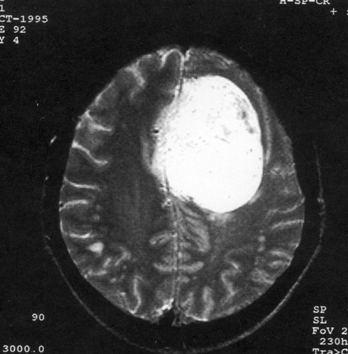

病历摘要:??患者女性,37岁。大便时突起炸裂样头痛3小时,伴喷射样呕吐。既往体健。体检:T37.5℃,BP145/90mmHg,R20次/分,P85次/...

问题 病历摘要:??患者女性,37岁。大便时突起炸裂样头痛3小时,伴喷射样呕吐。既往体健。体检:T37.5℃,BP145/90mmHg,R20次/分,P85次/分。神志清楚,颅神经检查无异常,颈强直,克、布氏征(-),四肢肌力、肌张力正常,病理征(-)。 为明确诊断,可考虑作什么检查?